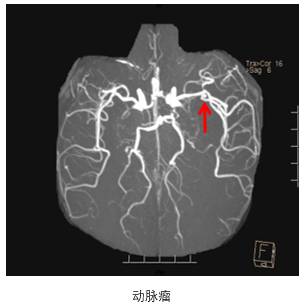

• 术后即刻:去碘CT排除出血风险,梗死灶出现。

• 术后一天:DWI显示梗塞面积没有明显增大,MRA提示血管再通,发现存在LMCA动脉瘤。

• 术后四天:CT显示没有出血表现,梗死灶已经形成。

• 术后3个月:复查CT显示恢复情况良好。